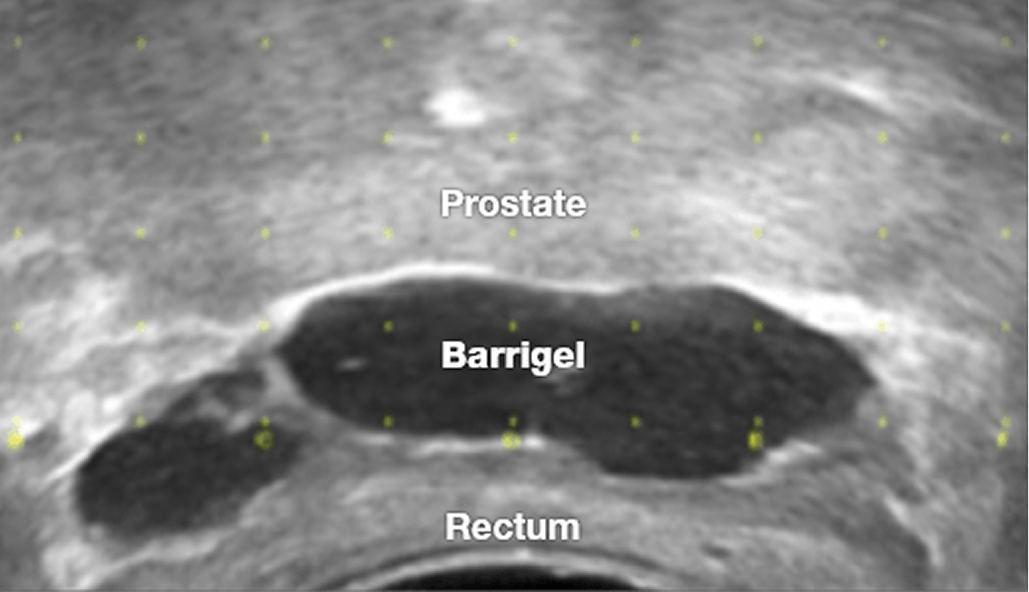

Modern prostate cancer treatment is effective, but radiation can impact healthy tissue located near the prostate. Barrigel™ rectal spacer helps protect the rectum by reducing the amount of radiation that reaches it during treatment.1

Many men with prostate cancer receive radiation therapy – however, radiation beams can potentially affect healthy tissue near the prostate and result in long-term radiation side effects like diarrhea, rectal pain, and bleeding. Due to its close proximity to the prostate, the rectum is at risk for radiation beam exposure.

By creating space between the prostate and rectum, Barrigel™ rectal spacer helps reduce unwanted radiation exposure to reduce rectal side effects.1